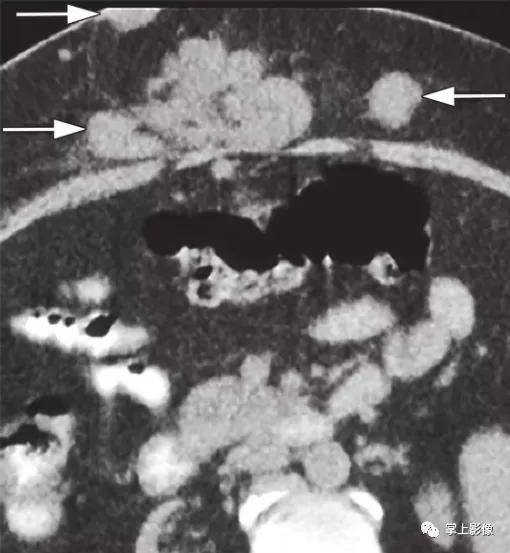

注射肉芽肿,46岁卧床不起妇女,每天皮下注射依诺肝素。CT显示多发注射肉芽肿(轮廓区)